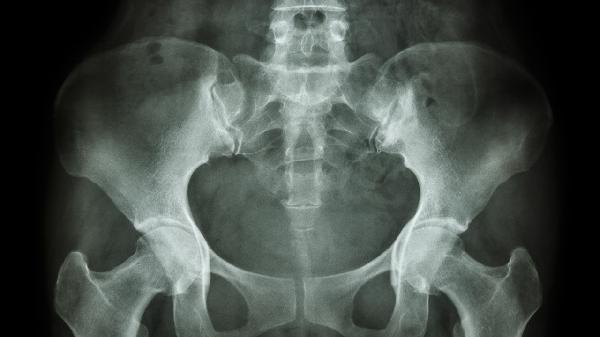

坐骨神经的治疗方法有哪些

坐骨神经痛的治疗方法主要有卧床休息、物理治疗、药物治疗、封闭治疗、手术治疗等。坐骨神经痛通常由腰椎间盘突出、梨状肌综合征、脊柱退行性病变、肿瘤压迫、外伤等因素引起,表现为臀部至下肢的放射性疼痛、麻木或无力。